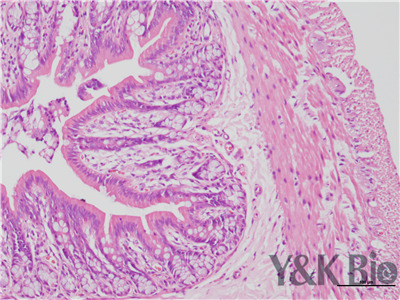

HE染色流程是什么,很多人都不知道,今天跟着小编一起来学习一下,切片的好坏直接影响疾病诊断的及时与准确性。因此一张高质量的HE染色切片,是实验室必须掌握的技术之一。HE染色目前在国内国外病理诊断上被

广泛采用,常规的染色方法。下面一起来看HE染色的基本顺序。一般切片的片子应在60-70度左右的烤箱中烘烤30分钟以才可以进行染色。总的来说是一个时间较长的过程。

1.样品制备

对于贴壁生长细胞,胰酶消化,调整细胞浓度约1×105/ml,滴加于盖玻片上(置于6孔板中),培养相应时间后,取出细胞爬片,用PBS 洗涤3次。2.样品固定 95%乙醇固定20min,PBS洗涤2次,每次1min。3.染核 苏木

素染液染色2-3min,自来水洗涤。4.分色 镜下观察,若细胞核染色过深,用1%盐酸酒精溶液分色数秒,自来水洗涤。 5.染胞质 浸入伊红染液染色1min,自来水洗涤。6.封片 吹干或自然晾干细胞爬片后,陕西中性树胶封片。

以上六点就是HE染色的基本步骤,大家可以参考一下哦 。